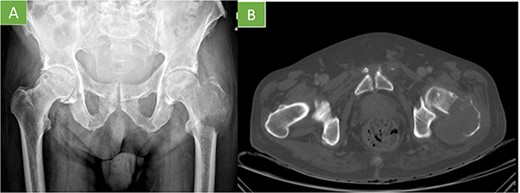

Bone scintigraphy of the entire skeleton, SPECT–CT of the pelvis (Fig. 2) and magnetic resonance imaging (MRI) was performed for surgical planning (Fig. 3A–C).

Bone scintigraphy of the entire skeleton with Tc99 and SPECT–CT. Highlighting of radioactive tracer in left proximal femur and sacrococcygeal region.